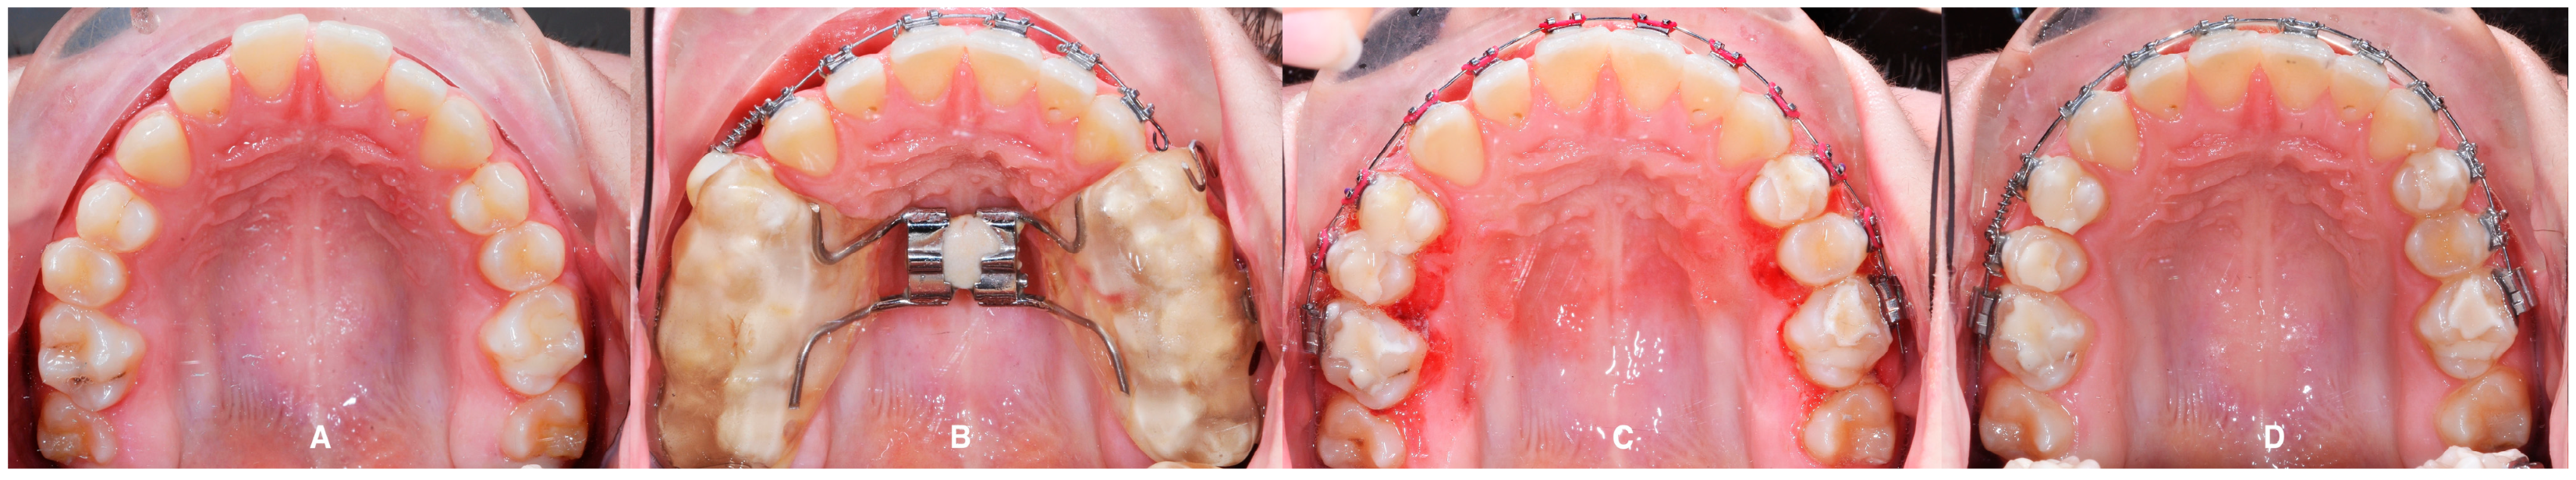

3. The Results of the Treatment